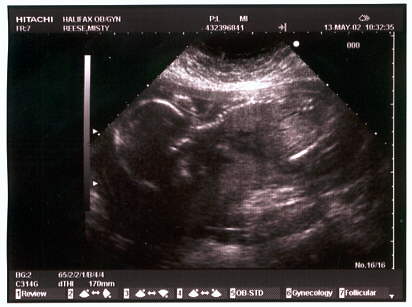

The ultrasound pictures (in May at 21 weeks):

Looking down with a good view of the spine.